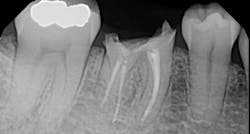

I began centering my consultation appointments on options that subsequently allowed patients to actually sell themselves on the implant treatment modality. I would present the tooth-replacement options of endo/core/crown, extraction/bridge, and extraction/implant ... and then I would explain the pros and cons of each. What I found is that patients overwhelmingly chose the root-replacement option—dental implants—over the old-school (drill-o-dontics) to reconstruct their missing tooth. Patients actually wanted an implant once they were armed with all the complete information they needed to make their decision. Having models on hand that show the difference between each option is highly effective, especially for those patients who are visual learners.

When your treatment plan includes only the next most conservative procedure—instead of all treatment options—inevitably you will do lots of work “saving” badly damaged roots and roots with guarded or poor long-term prognosis. Some patients may applaud or highly value these efforts on your part, but I have met many more who are glad to skip the possibility of re-treatment, root fracture, core failure, etc. You'll find that many patients will choose implants as an expedient and efficacious alternative to restoring the root with diminished or guarded prognosis, rather than spend their money over and over again on an undesirable tooth.